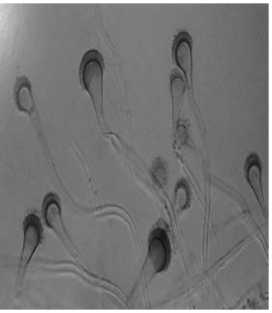

(1)菌体形态结构:镜下可见分生孢子头呈圆柱状,长短不一,分生孢子梗无色或绿色、光滑,近顶端膨大形成倒立的烧瓶样顶囊,顶囊上分布有单层小梗。烟曲霉镜下形态见图15-10及文后彩图。

图15-10 烟曲霉镜下形态(×400)